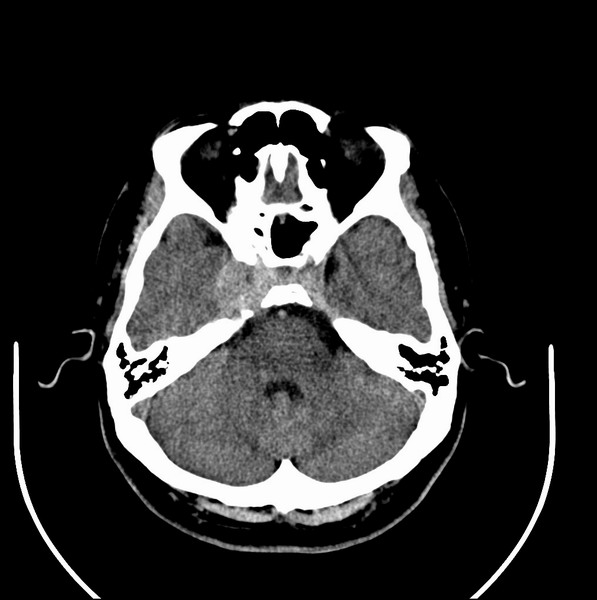

扫描示鼻咽腔不对称,中度狭窄,右侧咽隐窝消失,局部软组织肿块,鼻咽右侧壁增厚形成肿块,突入鼻咽腔,肿块平扫呈等密度,肿块向深部侵润,右侧翼内外肌受侵,右侧咽旁间隙变窄;向后生长,头长肌界线欠清,向后上生长侵犯同侧颈动脉鞘区。双侧海绵窦增宽,内见软组织影与鼻咽部肿块相连。考虑鼻咽癌。鼻咽癌主要是放射治疗,且效果较好;到当地有治疗设备较大医院治疗即可。

这个病例有点特殊,和常见的鼻咽癌不太一样,以向颅内侵犯为主,骨质破坏区小。鼻咽癌首先要考虑,有没有其他可能?本人不会看mr片,期待有人能讲解,期待病理。

鼻咽部新生物(纤维血管瘤?鼻咽癌?)侵犯右侧中颅窝底及右侧海绵窦;建议必要时活检定性。